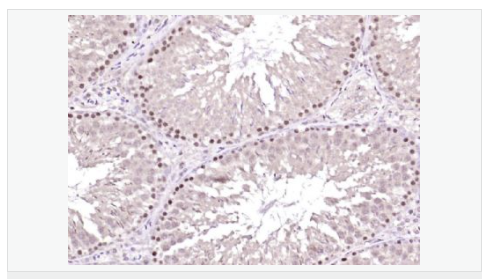

| 產(chǎn)品應(yīng)用 | ELISA=1:5000-10000 IHC-P=1:100-500 IHC-F=1:100-500 IF=1:100-500 (石蠟切片需做抗原修復(fù)) not yet tested in other applications. optimal dilutions/concentrations should be determined by the end user. |